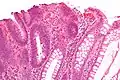

| Inflammatoire | Muqueuse/sous-muqueuse élevées avec inflammation | Si développement d'une dysplasie | Maladies inflammatoires chroniques intestinales, ulcères, infections, prolapsus muqueux | ||

| Adénome tubulaire (villositaire, tubulovilleux) | Glandes tubulaires avec des noyaux allongés (au moins à faible teneur atypie) | Oui | ![]() |

||